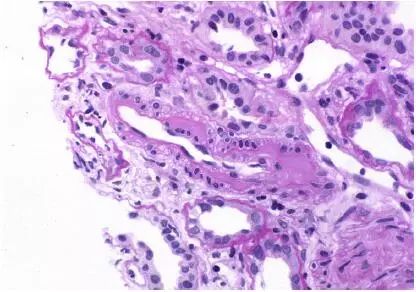

CNI肾毒性导致的血管收缩无形态学变化。急性CNI肾毒性特征包括:近端肾小管上皮细胞空泡化,大小一致;血管损伤,平滑肌细胞丢失;肌细胞胞浆空泡化;细胞坏死或凋亡退化。肌细胞损伤最终发展为局灶性结节性玻璃样变和透明样变,可延伸至小动脉和动脉血管壁整个中层。CNI肾毒性还可引起血栓性微血管病变(TMA),主要累及小动脉和肾小球毛细血管袢。慢性CNI毒性特征为:条状间质纤维化,肾小管萎缩。

近端肾小管上皮细胞空泡化,大小相等,内质网扩张,大型溶酶体。动脉中层和外膜透明质酸积聚。TMA患者可出现肾小球内皮细胞肿胀,内层扩张和肾小球系膜溶解。